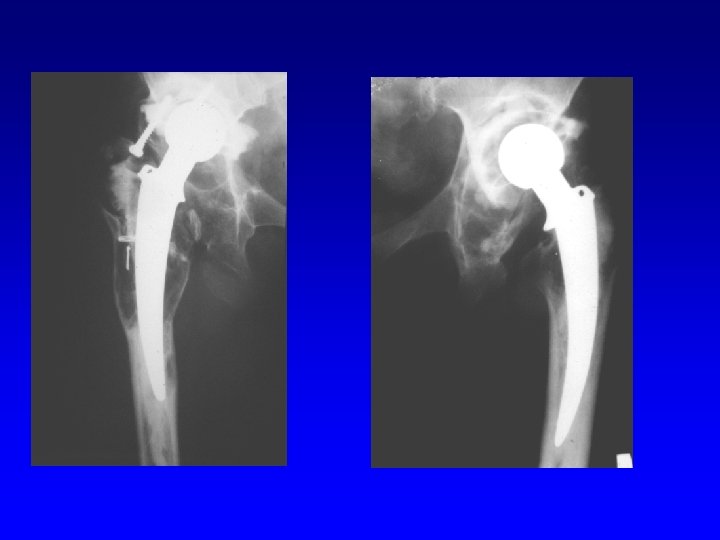

Revision THA

Revision of the acetabulum